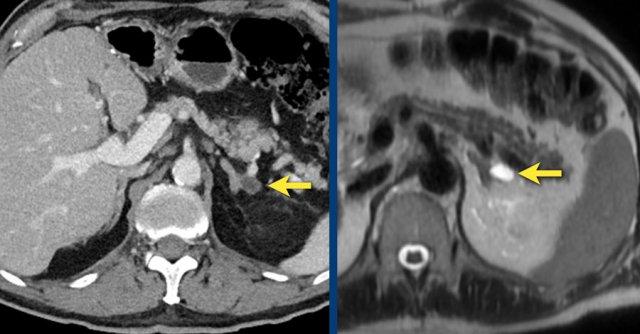

MRI được thực hiện cho tổn thương tình cờ tuyến thượng thận trái phát hiện trên CT không tiêm thuốc và pha động mạch ở bệnh nhân nam 61 tuổi có phình động mạch chủ bụng.

Trên CT không tiêm thuốc, tỷ trọng là 18 HU.

Ảnh T1 đảo pha cho thấy sự giảm tín hiệu không đồng nhất kín đáo so với ảnh đồng pha.

Lưu ý rằng chuỗi xung T1 có xóa mỡ không có giá trị trong việc phát hiện mỡ nội bào vi thể.

Tiếp tục xem các hình ảnh tiếp theo.

Vùng tăng tín hiệu trung tâm kín đáo trên chuỗi xung T1 xóa mỡ cũng tăng tín hiệu trên chuỗi xung T2W và không ngấm thuốc tương phản từ trên ảnh sau tiêm.

Sau khi so sánh với các hình ảnh CT trước đó từ nhiều năm trước, tổn thương được xác định là u tuyến phát triển chậm với xuất huyết nội u mới xảy ra.